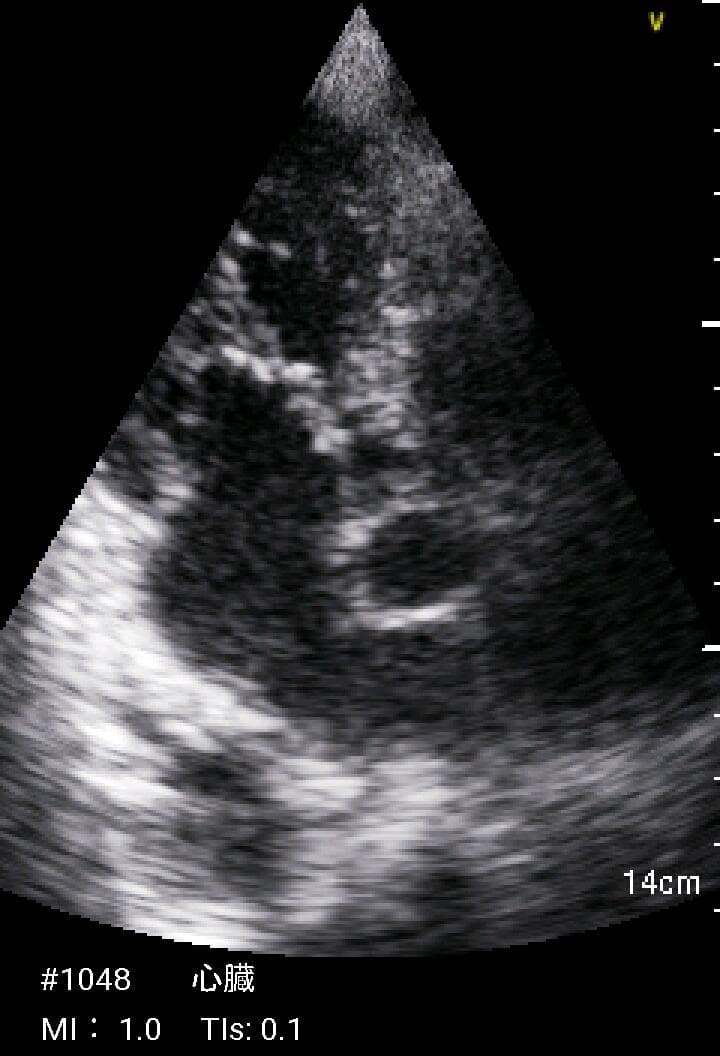

おわかりになる方のみの購入をお願いいたします実際に実施した写真をあげました正常肝臓、胆石症、頸動脈プラーク、同じく頸動脈プラーク、Mrの収縮期、同じくM弁の開放期とA弁の開放期、腹部大動脈瘤、正常の頸動脈、甲状腺右葉の結節、前立腺肥大画像の描出は条件によりますがご検討をお願いいたします経年変化、使用に伴うスレや傷などがあります機能に問題はありませんスキャンは心血管、腹部、体表に対応します外部接続端子のカバーが一部壊れていますが蓋は閉まりますバッテリーはフル充電されますが劣化はあると思います医療用モニタリング機器 Vscan Extend、GE- モデル名: Vscan Extend- ブランド: GE- 色: ホワイト- 機能: 医療用モニタリング機器ご覧いただきありがとうございます。。[新品未使用品]KT TAPE ブラック 25cm プレカット 150枚入